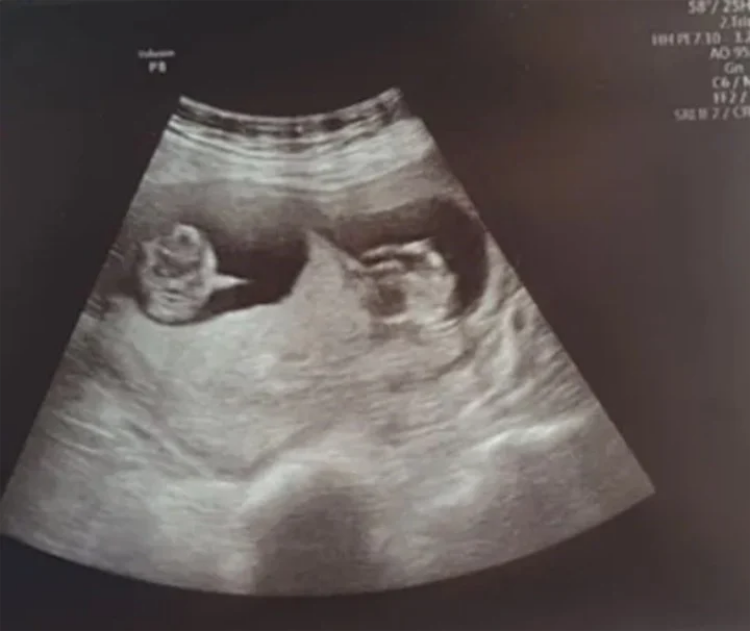

Esto fue lo que vivió una madre de origen irlandés que fue diagnosticada con coronavirus nueve semanas después de quedar embarazada. Por eso, tuvo que ser inducida en coma dos semanas antes del parto. El nombre de esta madre amorosa es Danielle Martin, quien temía lo peor para sus gemelas, debido a que los médicos habían advertido a la familia que era poco probable que las niñas lograran vencer al virus.

“Llamé al hospital para decir que necesitaba ponerme en contacto con mi pareja y un consultor se acercó al teléfono para decirme que la habían puesto en coma. Me quedé sin palabras, no sabía qué decir, era una locura”, señaló Bryan Green, esposo de Danielle. A pesar de todo, las gemelas se aferraron a la vida y nacieron llenas de salud mientras que su madre seguía en coma.

“Es un milagro para nosotros. Son nuestras princesas”, dijo Bryan Green. La investigación sobre el virus en mujeres embarazadas sigue en curso. Según lo que ya se sabe, las personas embarazadas pueden tener un mayor riesgo de sufrir una enfermedad grave de COVID-19, además de implicar mayor riesgo de resultados adversos del embarazo, como el parto prematuro.